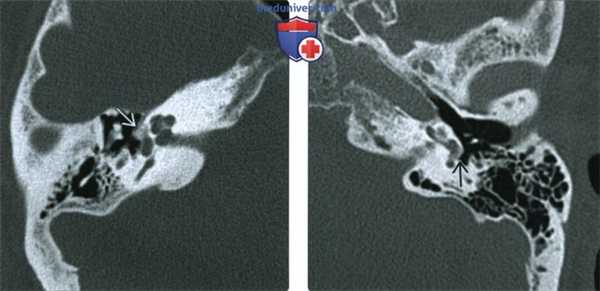

(Слева) При аксиальной КТ левой височной кости визуализируются типичные литические бляшки (сочетанный фенестральный и кохлеарный отосклероз). Пациенту была выполнена стапедэктомия с протезированием стремечка. Обратите внимание на протез стремечка с плотностью металла.

(Справа) При аксиальной МРТ Т1ВИ С+ FS у этого же пациента определяется контрастное усиление спереди от овального окна (щель перед окном) и вокруг улитки (фенестральный и кохлеарный отосклероз, соответственно).